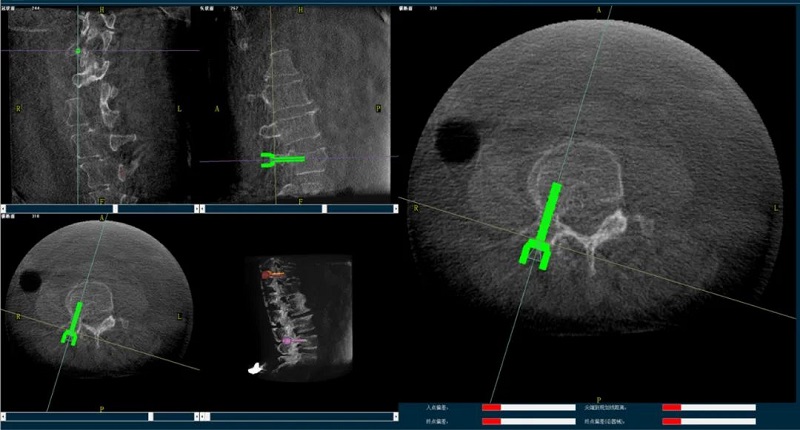

(2)医生制定个性化的手术方案,在机器人导航界面上进行路径规划;

(3)根据设定好的的位置和入针方向,植入引导针;